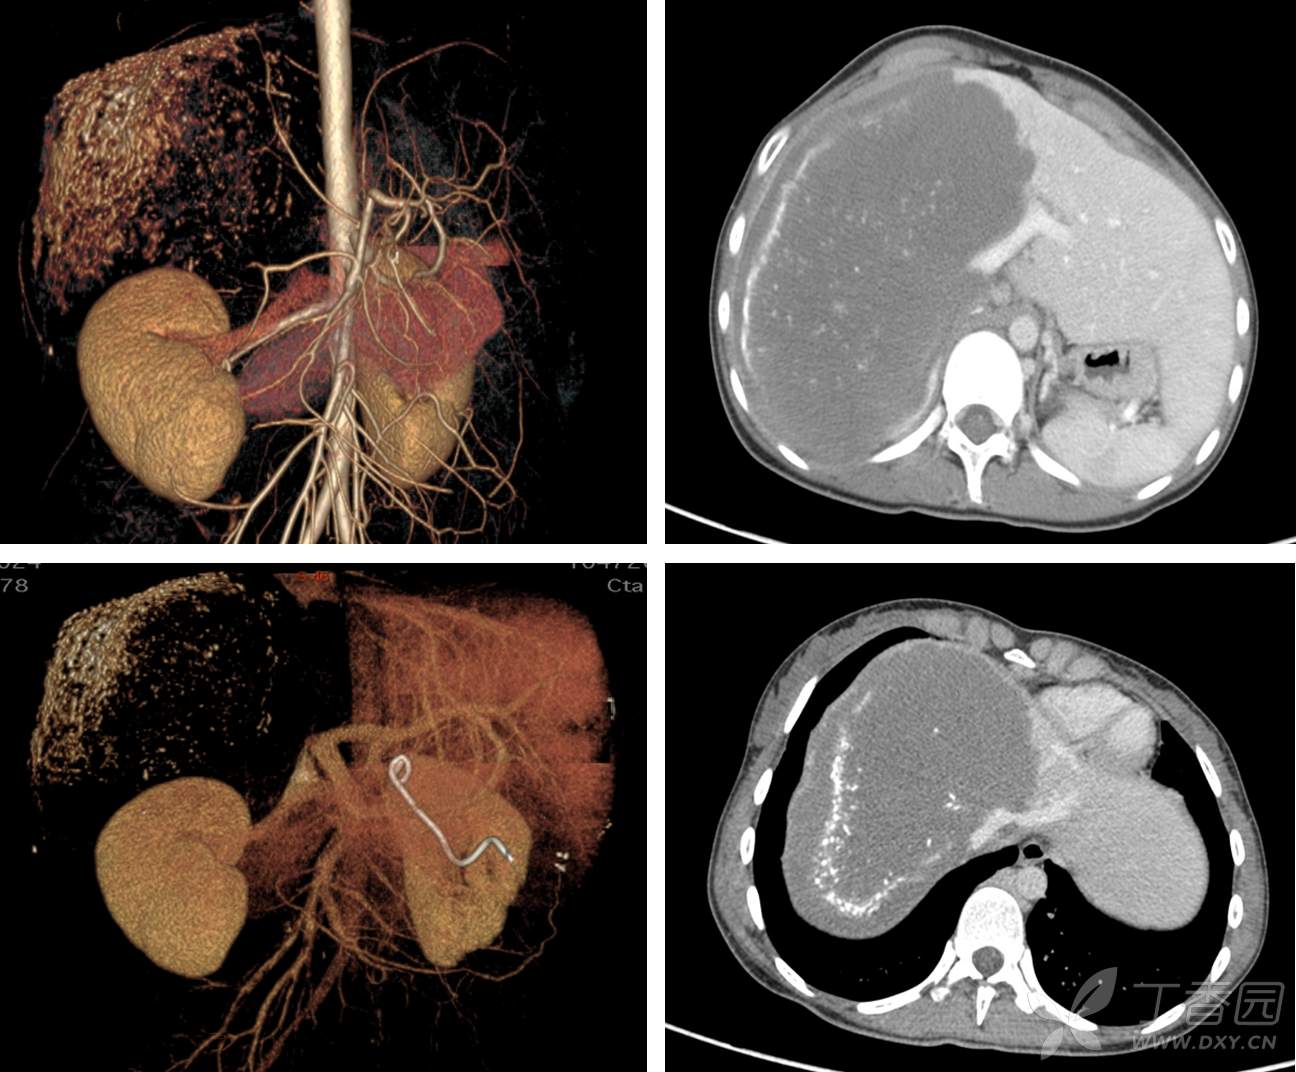

入院后予PTBD减黄,肝功能恢复正常。腹部增强CT提示:病变呈地图样表现,符合肝泡型包虫病特征;病灶主要位于肝脏右三叶,大小约12.1cm*15.4cm*19.2cm;病灶侵犯肝右动脉,门静脉右支全程及左支矢状部受侵,肝右静脉及肝中静脉全程受侵,肝左静脉-腔静脉汇合区受侵,肝中静脉与肝左静脉侧支循环开放,肝后及肝下下腔静脉严重侵犯闭塞,腹膜后侧支循环充分开放,肝左外叶代偿性增生。如图1:

图1 腹部CT血管成像:病灶位于肝脏右三叶,肝左外叶代偿性增生;肝动脉右支受侵,门静脉右支全程及左支矢状部受侵;肝右静脉及肝中静脉全程受侵,肝左静脉-腔静脉汇合区受侵,V2-V3存在侧支循环(蓝色箭头);肝后及肝下下腔静脉严重侵犯闭塞,腹膜后侧支循环充分开放(红色箭头)。

ICG-R15min 6.7%,肝功能Child A级,计算标准肝体积1076ml,左外叶体积1280ml,占患者标准肝体积的121%,剩余肝脏倒是够用的,那就剩一个关键问题,流入流出道完整性能否保证。

流出道:肝后下腔静脉全程受侵闭塞,纵向长度约9.5cm,好在腹膜后奇静脉及半奇静脉已代偿性扩张,因此术中可酌情仅行门腔分流,可不重建肝后下腔静脉。肝右、肝中静脉都已经没了,就连左肝静脉汇入下腔部也受侵,这使得在体切除几无可能,离体切除或许还有点希望。

流入道:左外叶的动脉是好的,门静脉左支较长,可切除重建。胆道系统和门脉一样,对于有丰富移植经验的医生,并非难事。